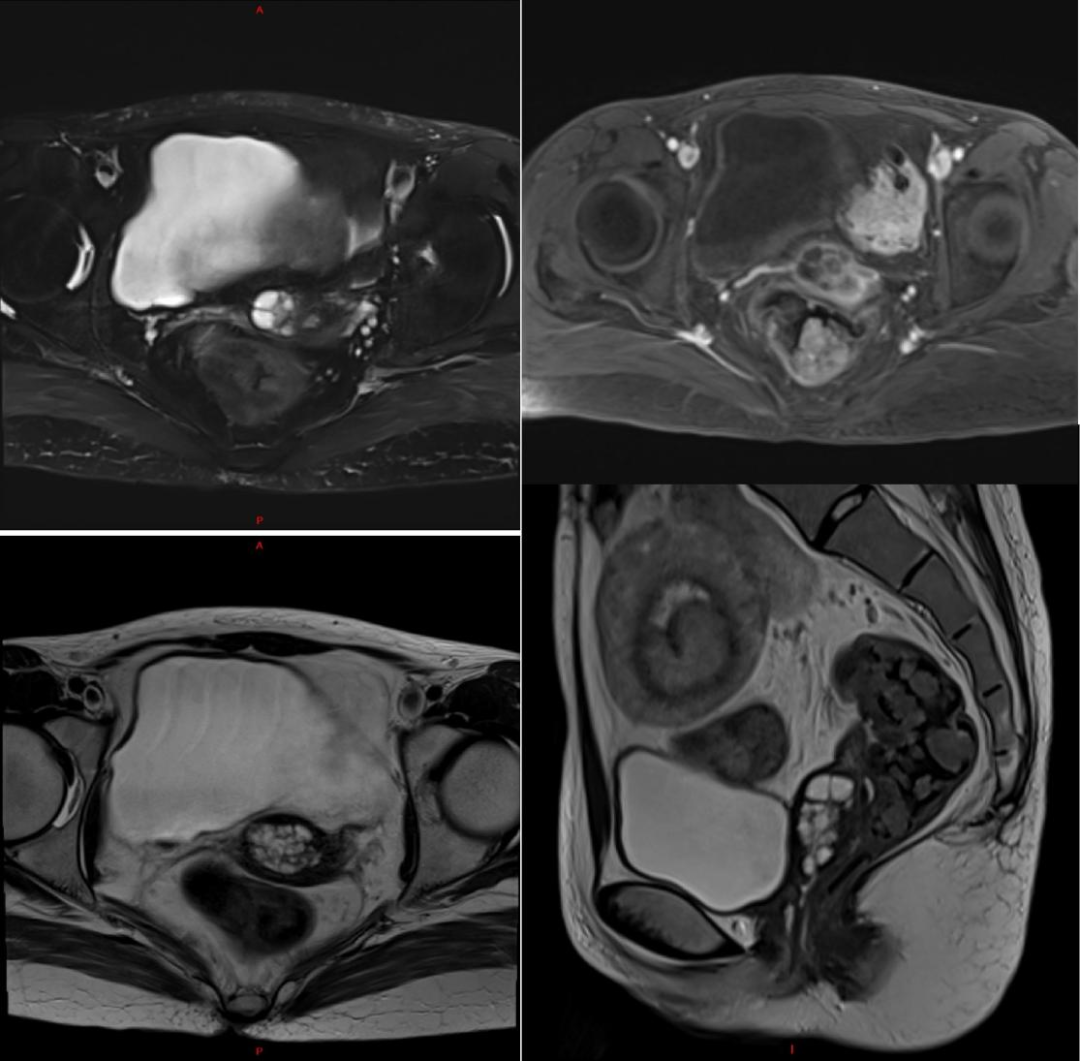

声检查  小器官超声提示甲状腺双叶多发囊性结节(C-TIRADS 2类)。乳腺及腋窝淋巴结未见明显异常。小肠CT三维重建(图1)提示:① 胃窦区、小肠、结肠多发结节肿块,符合P-J综合征影像学表现;② 左下腹肠套叠;③ 中度脂肪肝;④ 肠系膜根部多发肿大淋巴结;⑤ 肝左叶低密度结节,建议随访;⑥ 宫颈多发囊肿。

图1:十二指肠、空肠、回肠多发结节状密度增高影,左下腹肠套叠。

磁共振增强成像2025年12月15日,盆腔磁共振增强成像提示(图3):① 宫颈异常信号,考虑胃型腺癌,建议镜检或短期密切随访;② 双侧附件区多发生理性卵泡;③ 肠套叠;盆腔肠管内多发结节,符合P-J综合征表现。

图3:宫颈增大,可见多房囊状信号影,大小约3.1 cm×2.0 cm×3.6 cm,边界尚清。

2025年7月复查,妇科术后稳定。2025年12月患者于消化科复查,入院时乏力,间断出现双手、下肢痉挛及手足麻木感,食欲一般,体重较前下降,BMI:15.46 kg/m2,,呈贫血貌,颜面部及下肢水肿。实验室检查提示,血红蛋白 96.00 g/L,血小板计数 628.00×109/L,钾 2.51 mmol/L,钙 1.22 mmol/L,白蛋白 15.56 g/L,便潜血试验阳性。复查小肠CTE提示:① 消化道多发结节肿块,符合P-J综合征影像学表现;② 重度脂肪肝;③ 全子宫+双侧附件切除术后改变;盆腔及双侧腹股沟区多发较大淋巴结,同前相仿;④ 腹腔、盆腔积液,较前稍增多。